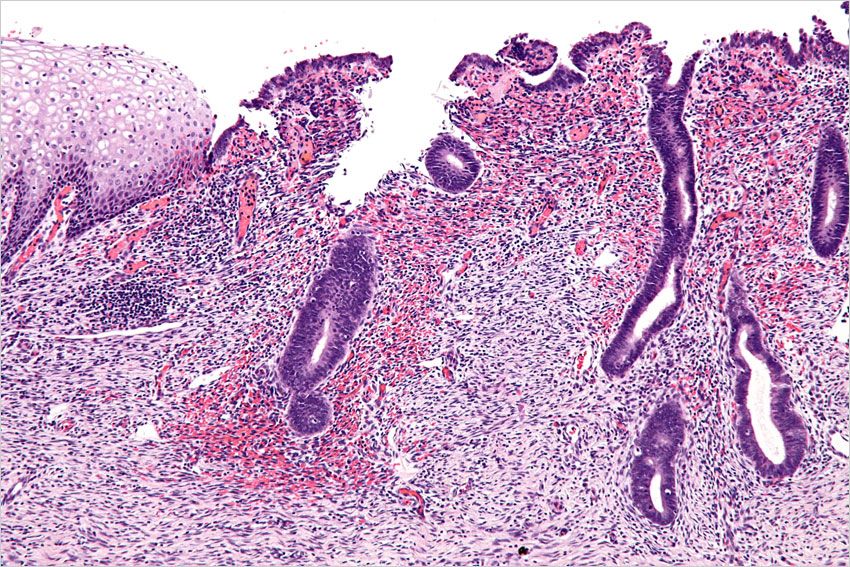

Les symptômes de l'endométriose, cette maladie caractérisée par la présence de tissu utérin en dehors de l'utérus, peuvent débuter dès l'adolescence mais sont parfois sous estimés.

C'est une maladie méconnue. L'endométriose touche une femme sur dix en France , et pourtant certaines femmes ignorent qu'elles souffrent de cette maladie qui fait que le tissu qui tapisse normalement l'utérus, se propage en dehors, sur d'autres organes et provoque des lésions, des kystes.